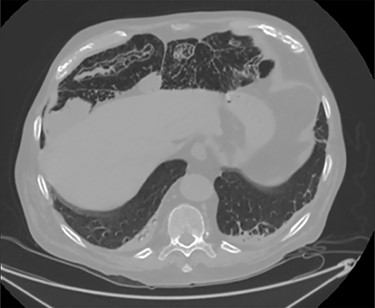

Unfortunately, once he returned home his temperature started to rise up to 38°C and he was readmitted to the hospital. A new contrast-enhanced Chest/Abdomen CT showed a bilateral pneumonia and a massive amount of intraperitoneal free gas, mainly in the abdominal upper quadrants (Fig. 2). No fat stranding, nondilated bowel, no vascular abnormalities and no free fluid were detected. Although the CT showed an evident worsening, the patient still remained completely asymptomatic on physical examination. Accordingly, he started to be treated with meropenem for pneumonia (Escherichia coli was isolated into the sputum) and he finally agreed to underwent diagnostic laparoscopy. Surprisingly, that was definitely not a case of pneumoperitoneum but an idiopathic PCI as we found multiple intramural air content cyst, about 2–3 cm in diameter, all around the small bowel loops and mesentery (Fig. 3). No intra-abdominal maneuvers were made. The patient had an unremarkable recovery (Clavien–Dindo classification grade was 1) [3] and he was discharged home on postoperative Day 15 in well condition, once he had recovered from pneumonia.

PCI was ultimately identified retrospectively using lung window settings.

PCI first documented by Du Vernoy in 1783 [4] refers to the intraoperative or radiological findings of intramural gas-filled cysts in the bowel wall (Fig. 4). PCI can easily mimic pneumoperitoneum on radiological imaging as CT, being a very sensitive examination, may show even minimal circumferential gas collections outside the bowel lumen or misrepresent some findings [5]. Liu et al. [6] found that PCI was misdiagnosed as a surgical abdomen in up to 27% of cases resulting in unnecessary operation. It is important to differentiate idiopathic PCI with a secondary form of this condition known as pneumatosis intestinalis which is not in fact a disease but a rare finding characterized by the presence of gas in the submucosal and/or subserosal of the bowel wall that may result from an underlying pathological process (Table 2). PCI has a reported incidence in general population of 0.03% on autopsy series and up to 0.37% in CT series. Its prevalence is still unknown [7]. However, Adachi et al. [8] in a retrospective, single-center study found 24.7% of PCI cases in the selected group affected by pneumoperitoneum. PCI involves most commonly the small and large bowel (respectively 42% and 36% of cases; in 22% is concomitantly present), but could also involve the mesentery and omentum [7]. Physiopathology remains still unclear although some hypotheses have been proposed such as: the ‘mechanical theory’ where an increased pressure of intraluminal gas secondary to mechanical problems breach the mucosal or serosal layers (i.e. blunt trauma, persistent vomiting, ileus or endoscopy); the ‘bacterial theory’ where an excess of intraluminal bacterial production of nitrogen gas diffuse through the bowel wall; the ‘chemical theory’ where malnutrition can prevent the digestion of carbohydrates and increased bacterial fermentation in the intestine; the ‘pulmonary theory’ that refers to increased intraluminal bowel pressure due to the respiratory system [9].